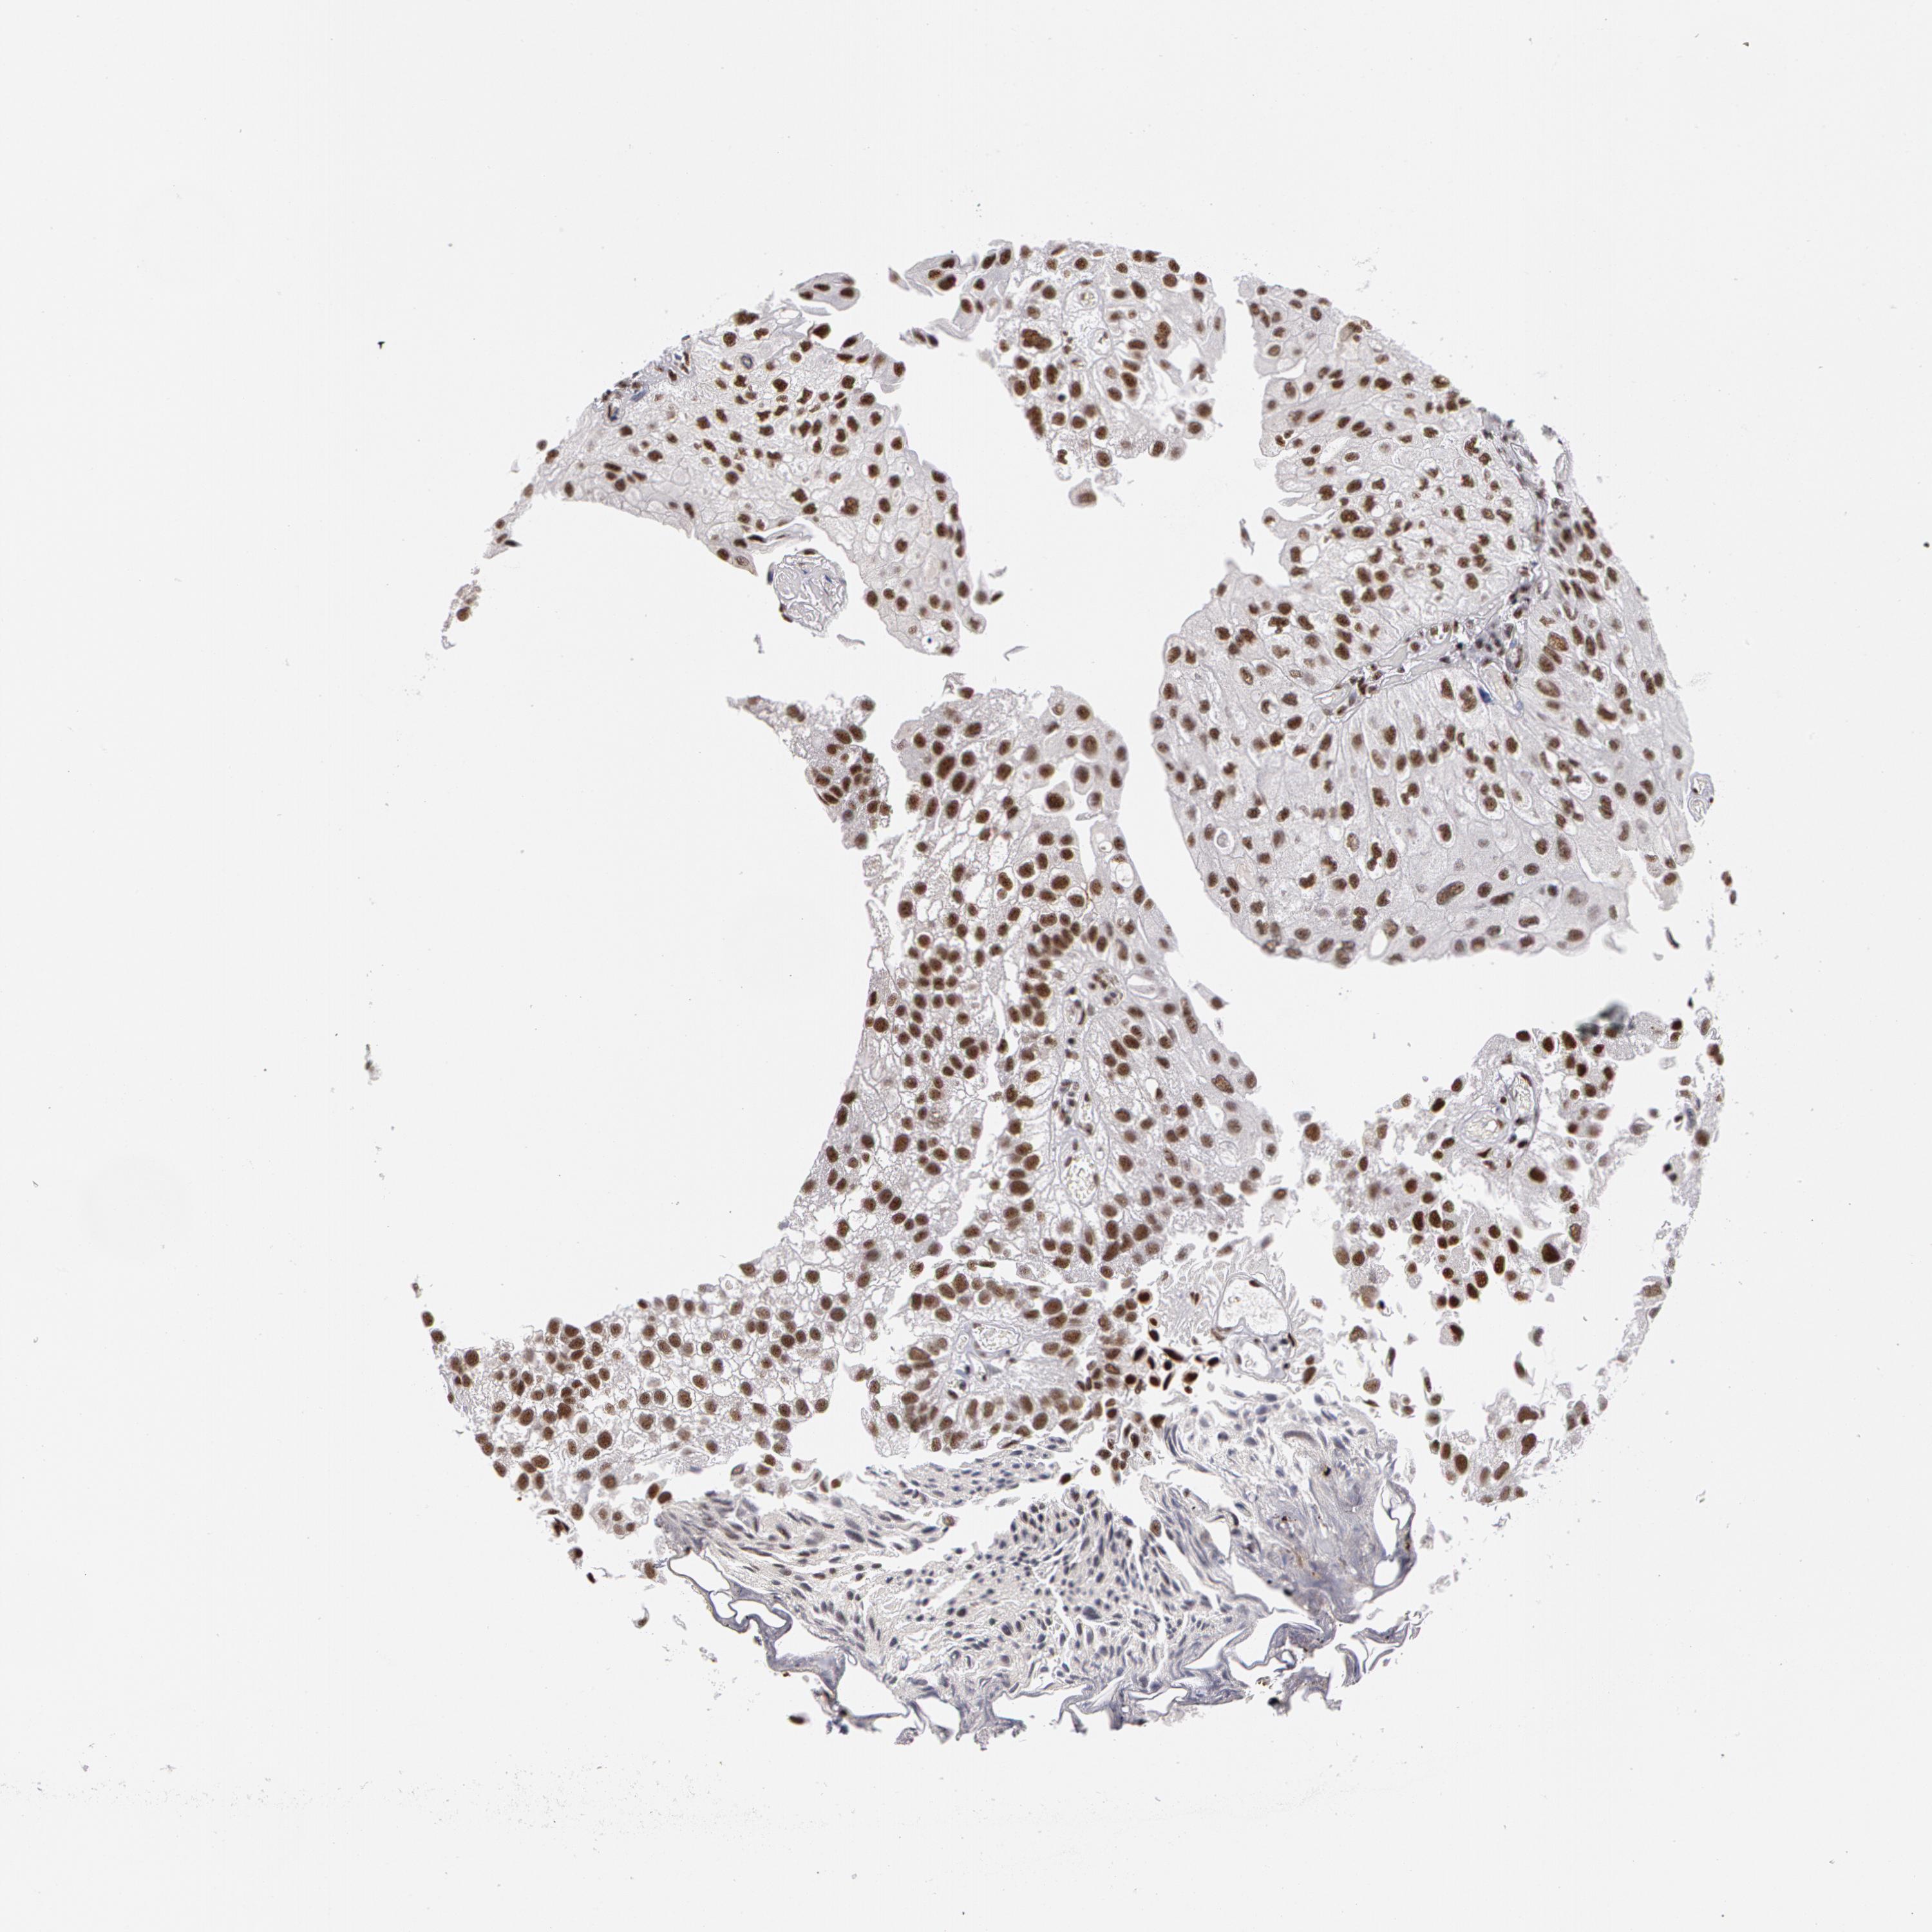

UROTHELIAL CANCER - Protein expressioni

A mouse-over function shows sample information and annotation data. Click on an image to view it in a full screen mode. Samples can be filtered based on level of antibody staining by selecting one or several of the following categories: high, medium, low and not detected. The assay and annotation is described here.

Note that samples used for immunohistochemistry by the Human Protein Atlas do not correspond to samples in the TCGA dataset.

Antibody stainingi

Antibody staining in the annotated cell types in the current human tissue is reported as not detected, low, medium, or high, based on conventional immunohistochemistry profiling in selected tissues. This score is based on the combination of the staining intensity and fraction of stained cells.

Each image is clickable and will lead to virtual microscopy that enables deeper exploration of all samples and also displays staining intensity scores, fraction scores and subcellular localization as well as patient and tissue information for each sample.

Antibody HPA001378

Staining

High

Medium

Low

Not detected

Intensity

Strong

Moderate

Weak

Negative

Quantity

>75%

75%-25%

<25%

None

Location

Nuclear

Cytoplasmic/membranous

Cytoplasmic/membranous,nuclear

Urothelial carcinoma, High grade

Urothelial carcinoma, Low grade